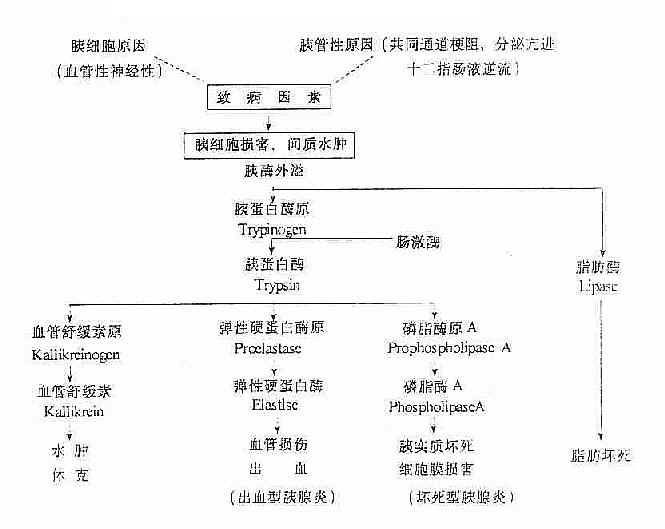

胰酶的激活与自身消化示意图